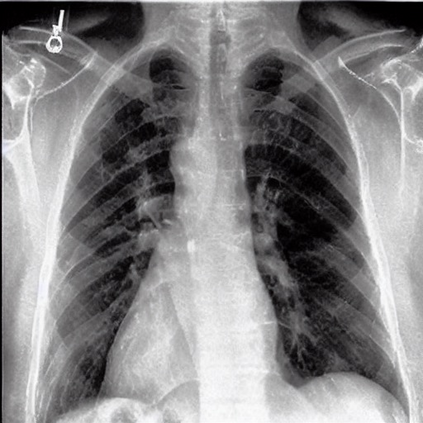

To address these issues, we propose a novel Adaptive patch-word Matching (AdaMatch) model to correlate chest X-ray (CXR) image regions with words in medical reports and apply it to CXR-report generation to provide explainability for the generation process. AdaMatch exploits the fine-grained relation between adaptive patches and words to provide explanations of specific image regions with corresponding words. To capture the abnormal regions of varying sizes and positions, we introduce the Adaptive Patch extraction (AdaPatch) module to acquire the adaptive patches for these regions adaptively. In order to provide explicit explainability for CXR-report generation task, we propose an AdaMatch-based bidirectional large language model for Cyclic CXR-report generation (AdaMatch-Cyclic). It employs the AdaMatch to obtain the keywords for CXR images and `keypatches' for medical reports as hints to guide CXR-report generation. Extensive experiments on two publicly available CXR datasets prove the effectiveness of our method and its superior performance to existing methods.